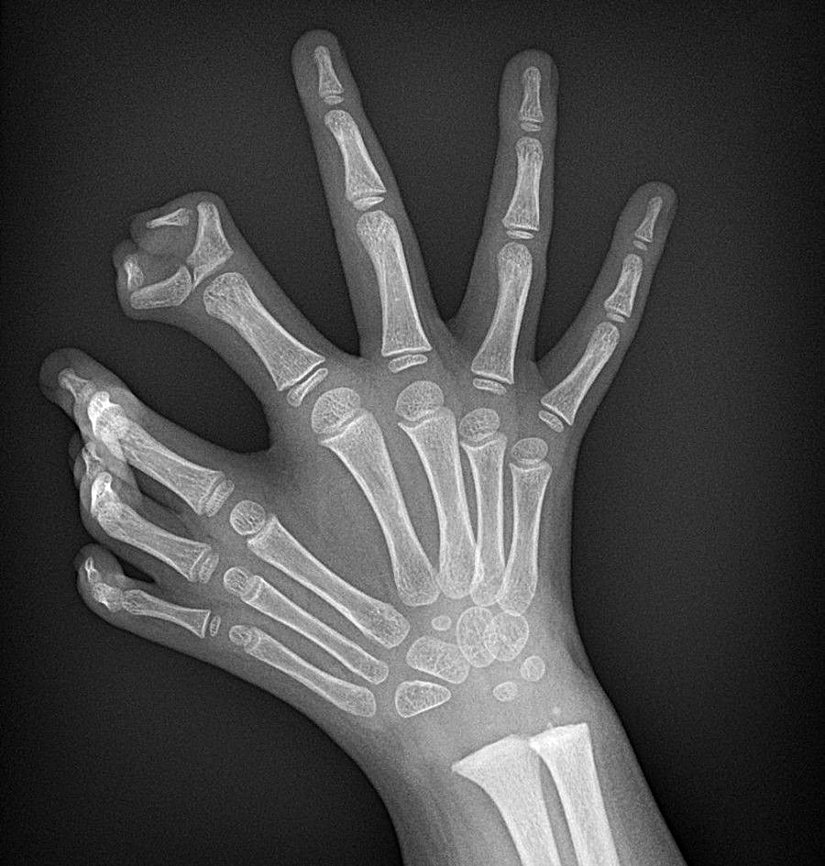

Bu gördüğünüz, "ulnar dimelia" adı verilen ve yaygın olarak "ayna el sendromu" olarak bilinen, nadir görülen kalıtsal hastalığa ait bir X-ray taraması görüntüsüdür. Bu hastalığa sahip kişilerin işaret parmakları ile başparmakları bulunmaz; bunun yerine diğer üç parmakları ayna simetrisine uygun bir şekilde çiftlenmiştir. Kişilerin ellerinin ayna görüntüsündeki parmaklar tam gelişmiş ve işlevseldir.

Hastalık, el ve kol gibi uzuvlarda gelişimsel anomaliler ve yamukluklar şeklinde kendini gösterir. Buna bağlı olarak bilekte de sertlik ve katılaşma görülebilir. Uzuvlardaki yamulma, kemiklerde meydana gelen uzunluk farklarına bağlı olarak yaşanır.